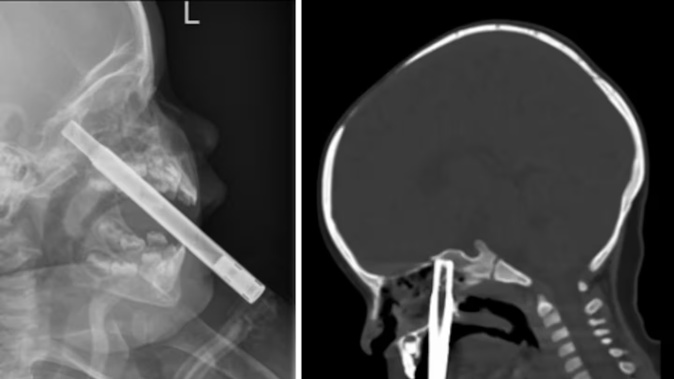

The specialists wrote that an X-ray was taken at the regional ED, which found that the straw had penetrated the girl’s nasal sinuses and was possibly sitting at the base of her skull.

A CT scan confirmed the tip of the straw was buried into the sphenoid bone, at the base of the cranium.

The 16cm long straw was removed by doctors after around six hours. Photo / NZMJ